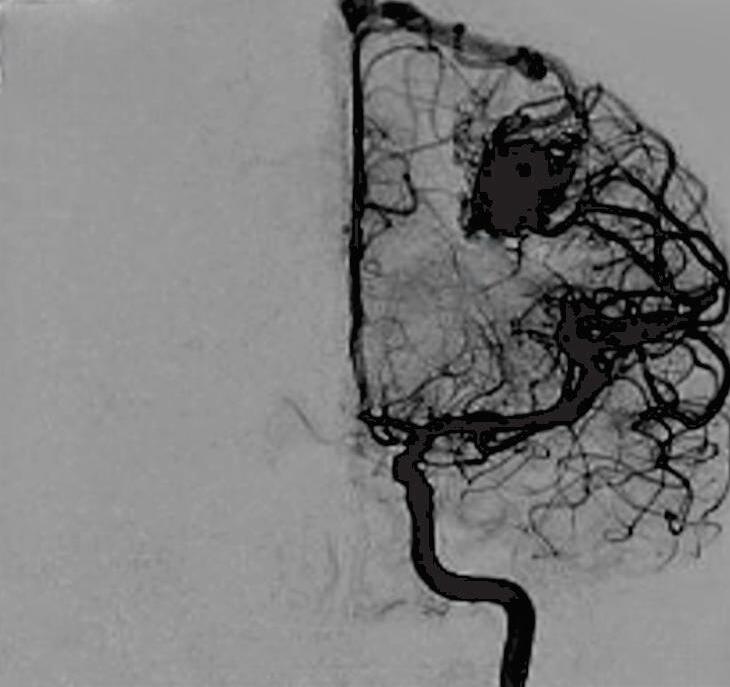

Com relação ao fluxo no interior do nidus, alguns autores classificam-nas em alto fluxo (Fig. 1-8) e baixo fluxo (Fig. 1-9). São consideradas de alto fluxo aquelas em que a opacificação após injeção de contraste ocorre apenas na malformação, em contrapartida, nas de baixo fluxo, ocorre opacificação da MAV e de outras artérias normais do mesmo território vascular. Exemplificando as lesões de alto fluxo temos as malformações arteriais, as malformações arteriovenosas e as fístulas arteriovenosas, enquanto as lesões de baixo fluxo são representadas pelas malformações venosas, linfáticas e capilares.25

Fig. 1-8. (a-c) RNM T1 com contraste, cortes sagital (a), coronal (b) e axial (c) demonstrando MAV não rota com nidus localizado no lobo occipital à esquerda (setas longas). (d) Arteriografia digital cerebral com injeção de contraste via carótida direita (AP) mostrando a contribuição da carótida direita na irrigação da MAV contralateral. (e,f) Com injeção de contraste via carótida esquerda, em Perfil e AP respectivamente, observa-se nidus compacto nutrido por ramos da artéria cerebral média à esquerda e a veia de drenagem precoce se dirigindo para o seio sagital superior. Projeções em AP (g) e em perfil (h) demonstrando a contribuição do sistema vertebrobasilar por meio de ramos distais da artéria cerebral posterior à esquerda e drenagem para os seios sagital superior e sigmoide à esquerda (setas curtas).